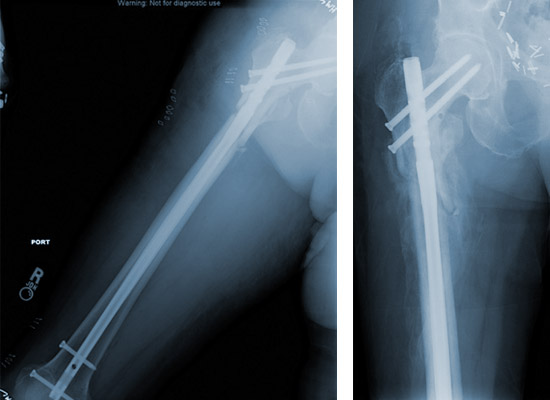

Femoral Reconstruction Nail Specification, Uses, Sizes and Surgical Techniques

Femoral Reconstruction Nail is designed to help treat various fractures of the femur. Different nails are available to be placed through the tip of the Greater Trochanter. Screws are placed through the nail to secure the implant in place and maintain length and alignment while healing occurs. The nails have multiple screw holes in the proximal body to allow surgeons to address different fracture types. Proximal and distal slots allow for compression or dynamization across a fracture.

Femoral Reconstruction nail

Your surgeon will push the femoral nail down the inside of the bone, either through a cut on the side of the hip or on the front of the knee. The nail goes across the break and holds it in position. The nail is held in the bone by locking screws that pass through holes in the nail. If you have an open fracture, your surgeon will clean the skin wound thoroughly during the operation to reduce the risk of infection. If the skin is badly damaged, you may also need one or more plastic surgery operations. At the end of the operation, your surgeon will close the skin with stitches or clips.